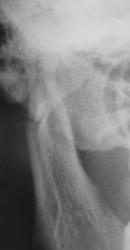

А это визави.

на мой взгляд здесь перелом суставного отростка